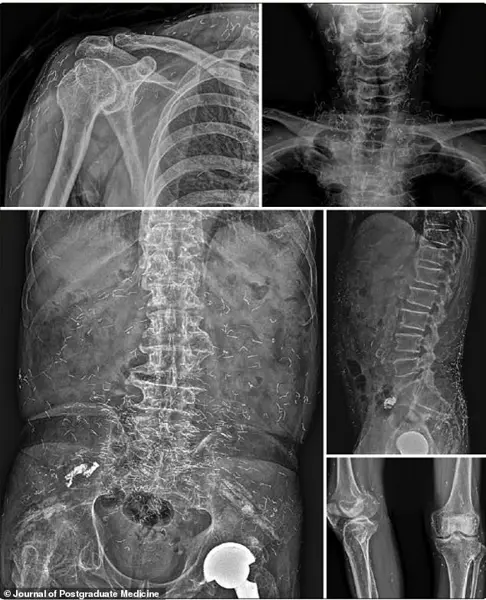

A 73-year-old Korean man was hospitalized for a stroke.

During his evaluation, he described a 30-year history of widespread joint pain, which he had self-treated with gold thread acupuncture.

X-rays revealed thousands of the embedded threads throughout his body, a testament to the long-term accumulation of these foreign objects.

His symptoms finally improved only after he received proper medication for his newly diagnosed rheumatoid arthritis—a condition he had unknowingly masked for decades by relying on an unproven therapy.

In the 73-year-old man’s case, years of unexplained joint pain were attributed to a self-diagnosed condition, delaying the detection of rheumatoid arthritis—a chronic, autoimmune disease that attacks healthy joint tissues.

His eventual diagnosis came only after the discovery of the thousands of gold threads, a revelation that forced him to confront the true cause of his suffering.